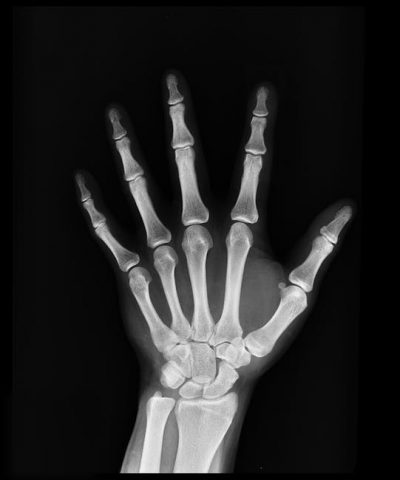

Numită și “boala oaselor fragile”, osteoporoza este caracterizată prin scăderea densității osoase, determinată de un proces de demineralizare (pierderea calciului și fosforului din os). Prin alterarea microarhitecturii țesutului osos, crește fragilitatea osoaselor și, în consecință, crește și riscul de fractură. Fracturile legate de osteoporoză pot apărea în orice os al scheletului cu un grad de invaliditate mai mare sau mai mic, cu posibilitatea de intervenție chirurgicală sau nu. (Elena Oceanu).